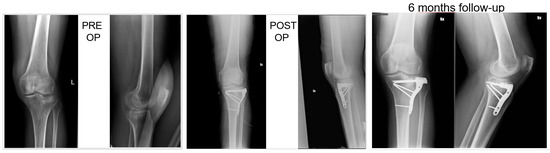

2.3. Surgical Technique and Rehabilitation

All patients had surgery within 48 hours from injury, after administration of spinal or general anaesthesia. A tourniquet was routinely positioned before starting surgical procedure; all patients were operated in a supine position, with injured leg in semi-flexion. Fractures were reduced through a percutaneous or open approach, depending on the cases; SB blocks, which size and shape were customised during surgery considering the features of bone defect for each singular patient, were positioned through a minimally invasive approach via the bony window exploited for reduction; finally, fixation of fracture line and implant were performed with screws and plates (see exemplificative Figure 1, Figure 2 and Figure 3). In one case fixation of the plateau fracture occurred through an arthroscopic approach. All the patients included in the study had identical post-operative regimen. Active knee mobilization and static quadriceps exercises were encouraged from the third day after surgery. Partial weight bearing was allowed at 4–6 weeks after surgery, and progressively increased to achieve full weight bearing at 12 weeks. Prophylaxis for thromboembolic events was obtained through administration of 4000 IU/day of low molecular weight heparin (LMWH) (enoxaparin), until full weight bearing was allowed.

Patients were clinically and radiologically assessed before surgery, at 2 weeks, and then at 1, 2, and 6 months, and 1 year after surgery. Same radiologist carried out the imaging, while evaluations were pooled by different clinicians. Clinical assessment consisted of a visual analogue scale (VAS) for the evaluation of pain, where patients were asked to report the level of pain during the day life activities; measurement of the range of motion (ROM) of the knee joint; and objective examination, intended to highlight possible alterations of surgical scar, vascular and nervous deficits, as well as infectious complications. Moreover, at 1-year follow-up Tegner Lysholm Knee Scoring Scale [21] and International Knee Document Committee 2000 (IKDC 2000) [22] questionnaires were administered during control visits, in order to evaluate patients’ subjective perception of knee function. One year after surgery, patients answered to the Short Form (36) Health Survey (SF-36) questionnaire, which scores the general physical and mental health on the basis of eight scales each ranging from 0 to 100 [23]. Radiological assessment contemplated the acquisition of anteroposterior and lateral projections radiographs at each follow-up. Images were examined in order to evaluate various features of healing process, like callus formation and maintenance of fracture reduction; as well as to detect the presence of possible malalignment, pseudo-arthrosis, bone non-unions, and articular surface depression or widening (see exemplificative Figure 1, Figure 2 and Figure 3).

At six months, X-rays images showed that all 34 fractures displayed a good consolidation rate, as confirmed by radiological reports. In particular, radiolucency of the xenografts was assessed [20], which became progressively more similar to that of the surrounding healthy bone tissue (see exemplificative Figure 1, Figure 2 and Figure 3 and comparative images in Figure 4).

Comparison with the current literature is challenging, due to the lack of standardised follow-up protocols and differences in quantitative assessment of outcomes among the studies. However, the implant of SB in our series resulted in a standard return to knee mobilisation, as highlighted by the mean ROM at last follow-up and the return to partial weight bearing at 4–6 weeks. We also described no complications, like infections and joint subsidence, if compared to similar studies present in the medical literature [31]. Radiological follow-up did not show diastasis or depressions of tibial articular surface excluding the incomplete subchondral reductions documented at the first post op X-ray, which means that mechanical properties of SB were adequate for high and complex forces which the plateau commonly undergoes. At each follow-up, the radiolucency of implants was progressively more similar to radiolucency of the surrounding bone (see exemplificative Figure 1 and Figure 2). We interpreted this evidence as supporting the thesis that SB would have been able to integrate with autologous bone tissue, favouring deposition of new bone matrix within an ongoing remodelling process: indeed, there is a clear morphological pattern on the evolution of the standard X-Ray imaging series over time which shows the substitution of the grafted material with a more homogeneous signal in the area of graft implant. As already demonstrated, the progressive remodelling together with an increase of the mineral signal cannot be dependent on the active remodelling of the graft per se given it is a decellularized matrix. Therefore, the increase in the density over time depends on novel mineral matrix apposition likely induced by the graft, as previously shown both in vivo and in vitro [7,20].

Figure 2. Sixty-year-old patient, X-rays: preoperative, postoperative and control at 6 months follow up of a Shatzker type 3 fracture, AO 41 B 1.3.